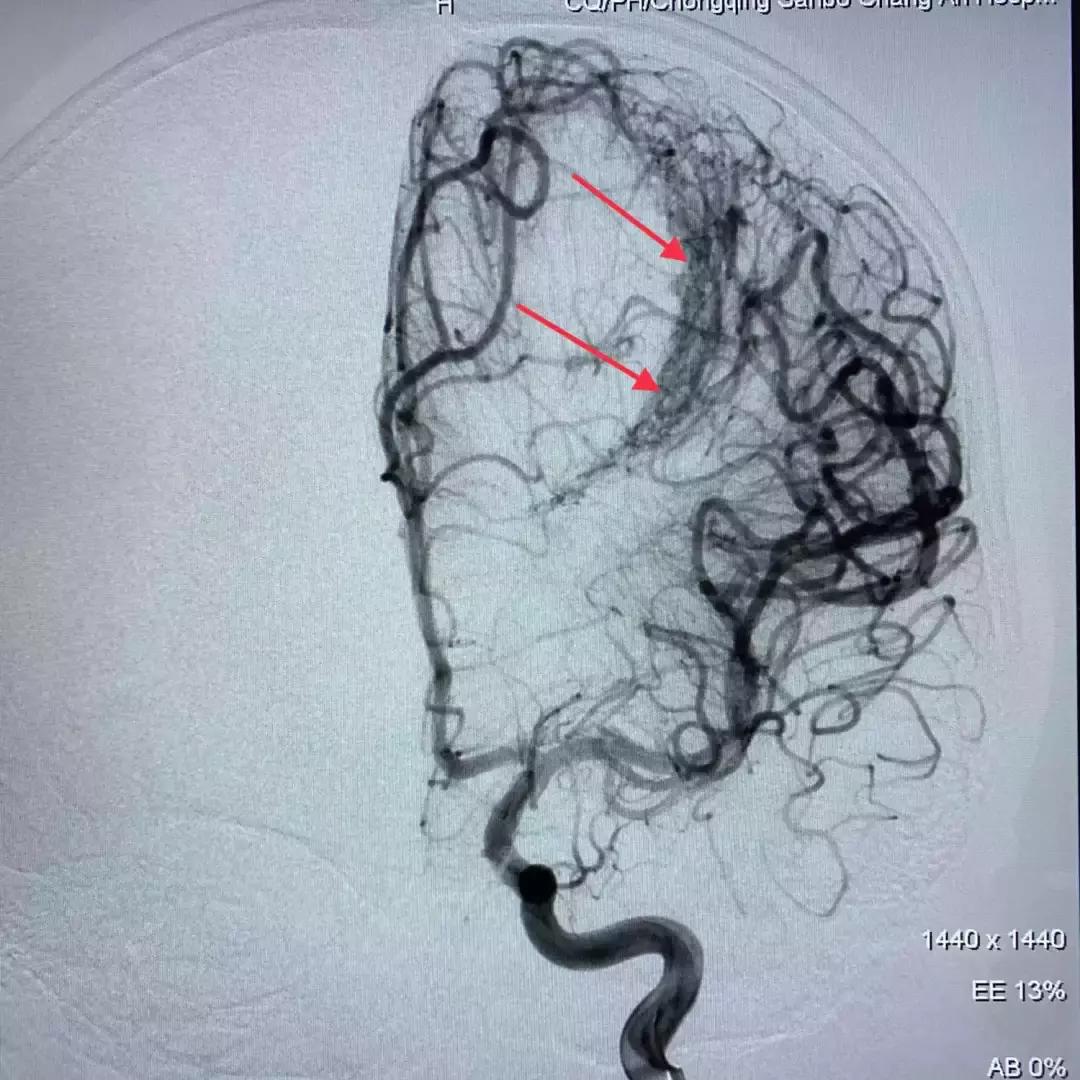

DSA脑血管造影提示脑血管畸形

从造影图上可以看到,畸形不大,但在脑子深部,位于功能区;正位像形似月牙,侧位看很弥散;而且均为终末细支或者细小侧支供血。经过和首都医科大学三博脑科医院刘加春教授远程会诊讨论,决定先给患儿实施栓塞治疗,这样既可以降低再出血概率,又可以尽量避免开颅手术造成的新的脑组织损伤,为小强的功能恢复最大限度创造条件。